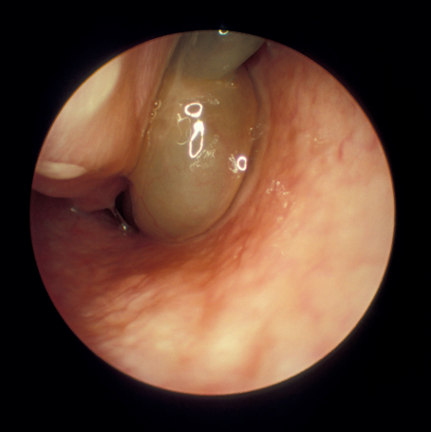

o   Occasionally, mucopus or polyposis may be visible, indicating chronic rhinosinusitis (usually these are not visible without an endoscope):

Nasal Polyp.png

Nasal Polyp